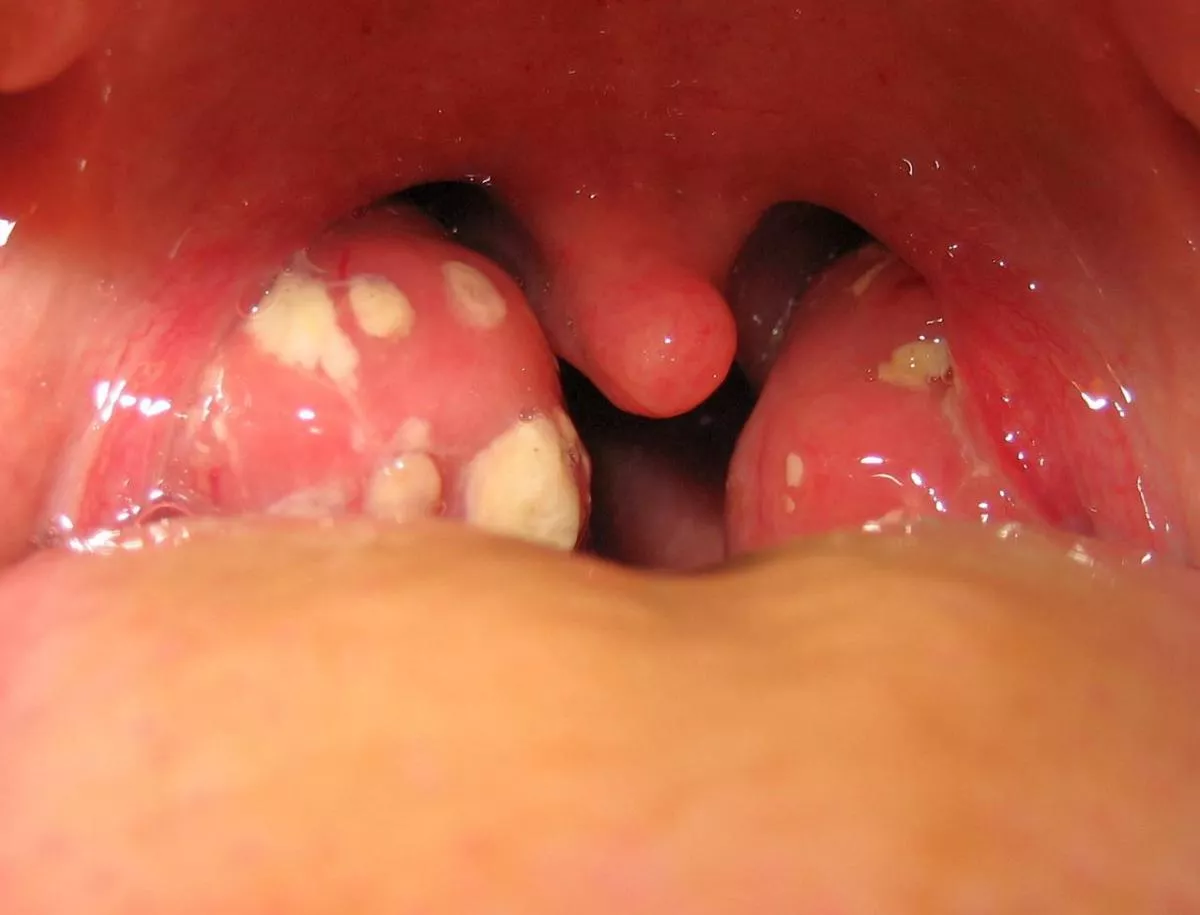

Mandulagyulladás (Tonsillitis). Gyulladt, megnagyobbodott mandulák, follikulusokból ürülő gennyes váladékszigetekkel. Gyulladás nélkül a follikulusokban morzsalékony, magától olykor nehezen távozó törmelék (detritus) lehet jelen. A tüszős mandulagyulladást baktérium, többnyire a Streptococcus pyogenes okozza.